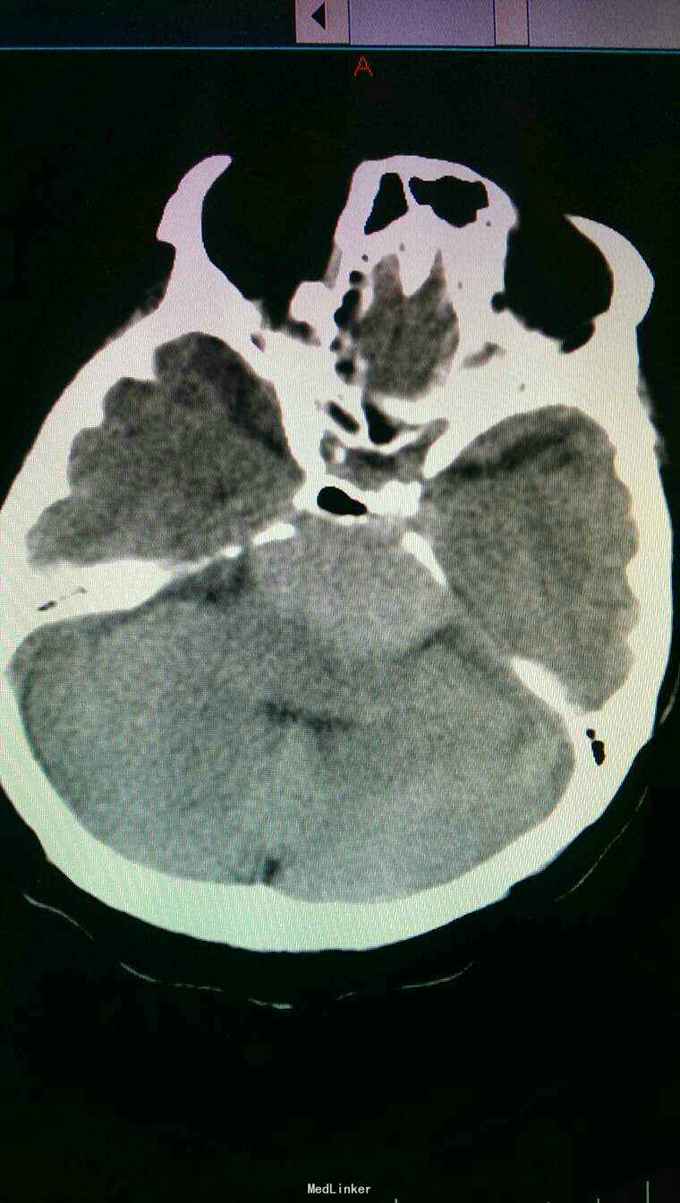

入院诊断:岩斜区脑膜瘤。完善术前准备,于全麻下行右侧颞下入路,岩斜区肿瘤切除,术中保留拉贝静脉,剪开小脑幕,近全切除肿瘤。

患者术后病情稳定,岩斜区位于颞骨岩部背面与枕骨斜坡部的岩斜裂汇合处,从岩骨尖至颈静脉孔。内侧至斜坡中线,外侧至第Ⅴ、Ⅶ和Ⅷ脑神经,上缘为鞍背,下缘为颈静脉孔水平;下方为枕骨大孔区。岩斜区脑膜瘤由于位置深,毗邻重要解剖结构,很难实现肿瘤全切除,且有较高的术后致残率,一直是神经外科手术的治疗难点。颅内脑膜瘤约0.3%~1.0%起源于岩斜区,是岩斜区最常见病变。它向上可侵犯岩骨尖、小脑幕、Meckel腔、鞍旁和海绵窦;向下侵犯内听道和颈静脉孔;向内侧达脑干和椎-基底动脉。当肿瘤很大时,可包绕同侧Ⅲ~Ⅺ脑神经。患者临床可表现头痛、复杂的脑神经麻痹、共济失调等症状,严重者表现为偏瘫、认知功能障碍。岩斜区脑膜瘤多数表现良性过程,目前,仍以手术切除为首选治疗方式。 岩斜区脑膜瘤手术技术非常关键,需要熟悉岩斜区解剖关系并有丰富的显微操作经验。在术前放置腰穿引流,或术中甘露醇应用可明显降低脑组织压力,减少牵拉造成的副损伤。提前对脑膜瘤基底的处理可有效避免肿瘤持续出血造成的蛛网膜界面消失。肿瘤的生长将神经、血管拉伸或包绕,尤其是复发的肿瘤,会破坏蛛网膜界面,侵犯脑干软脑膜。手术时应仔细分辨和保护。肿瘤囊壁与神经、血管外膜和脑干粘连,不应勉强分离,以保护下方结构。 待术后平稳复查头Ct。